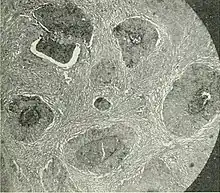

| Barthlin carcinoma tissue cross section | |